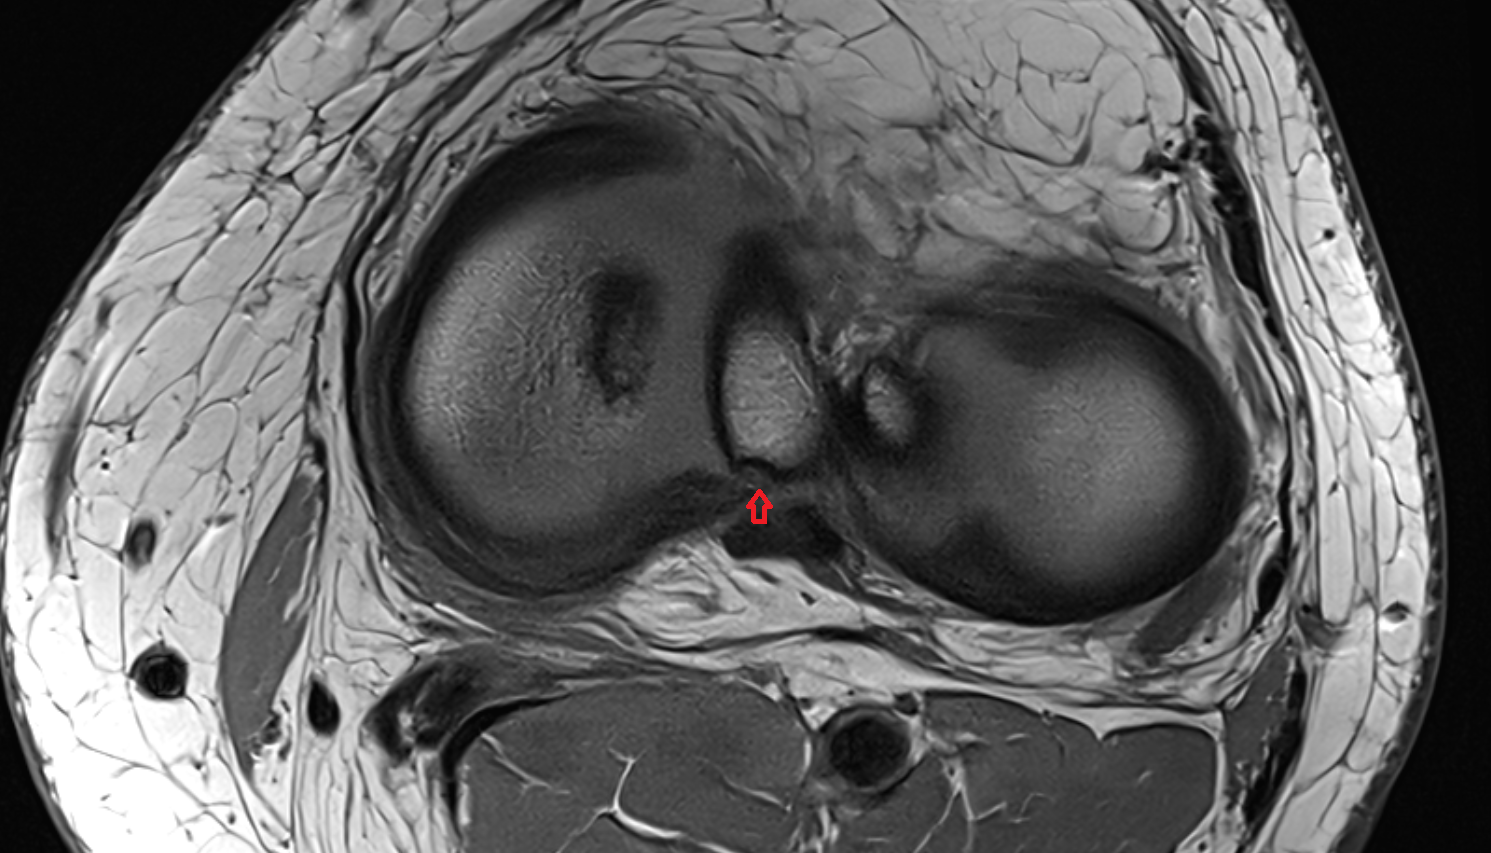

- Anterior cruciate ligament

- Posterior cruciate ligament

- Knee Joint